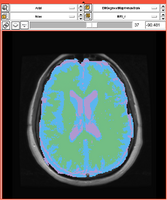

Existing Tasks in Slicer 3.6.3

Task 01: MRI Human Brain for non-skull stripped T1 scans

Task 02: MRI Human Brain Parcellation for skull stripped T1 scans

Task 03: Non-Human Primate for skull stripped T1 scans